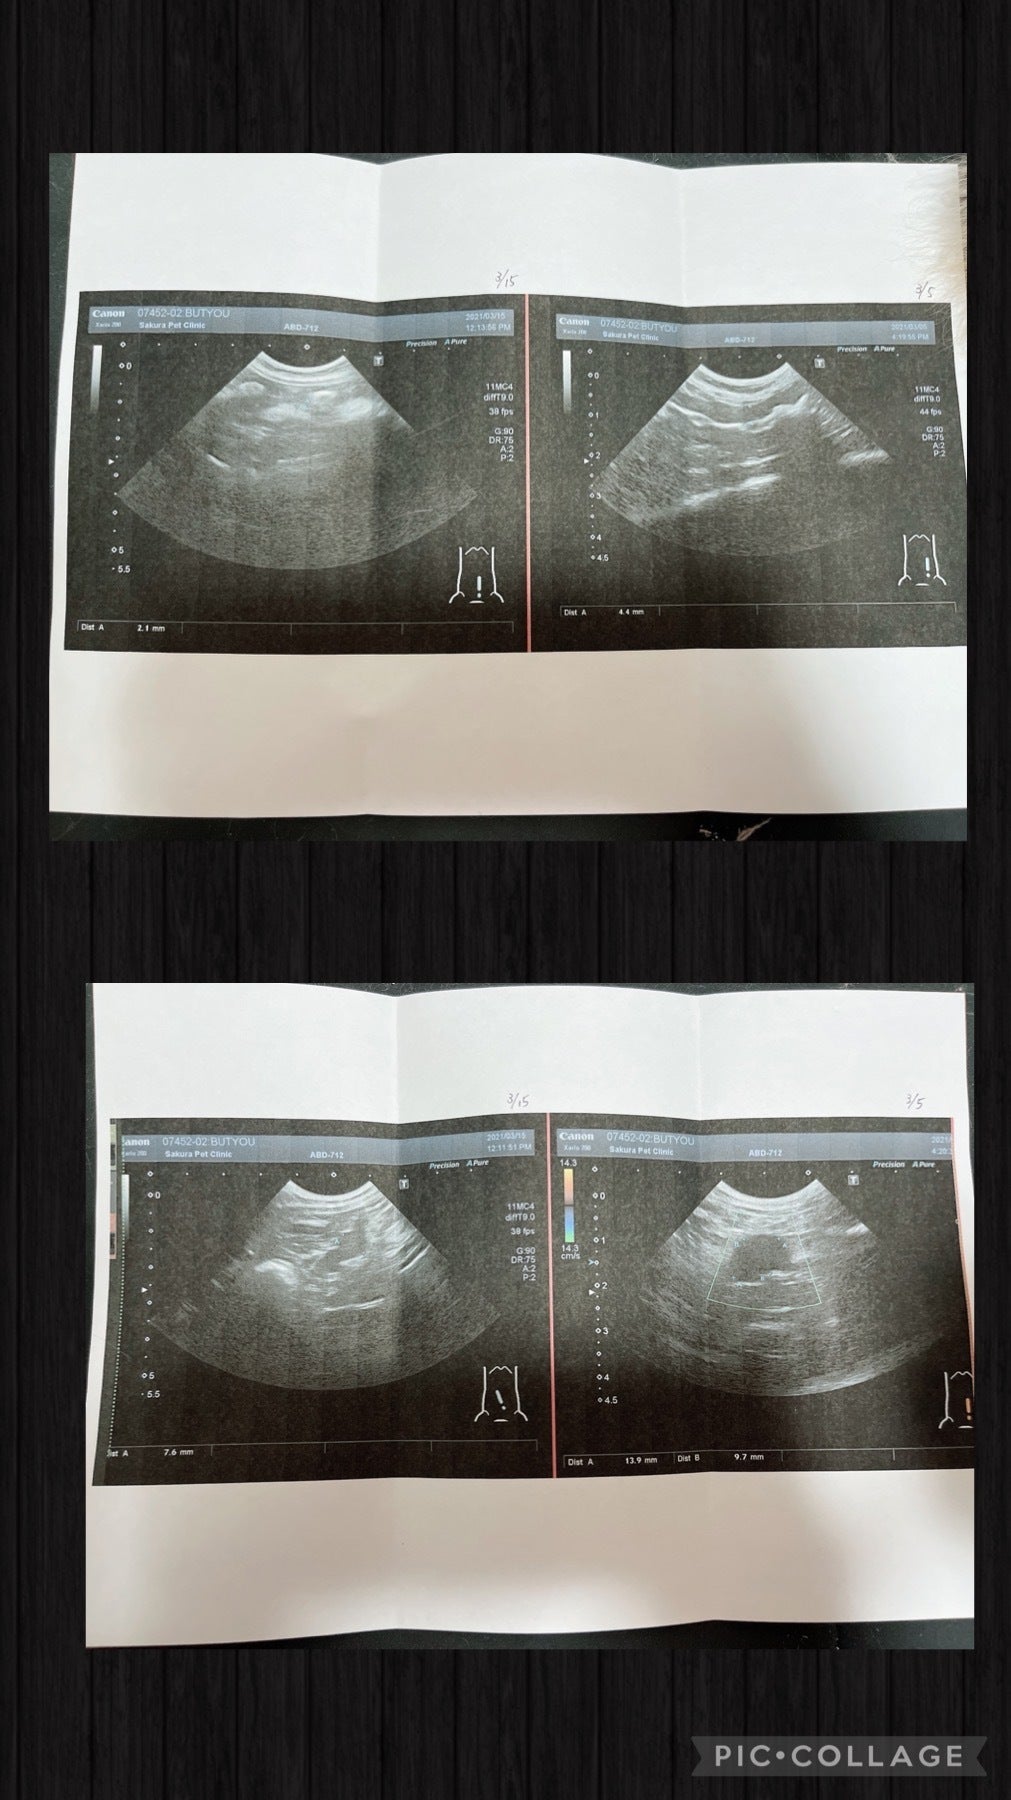

エコーを見てもらうとFIPドライタイプの疑いがあると言われました。

そこでもFIPドライタイプ初見疑いがあると言いわれ、その日はステロイド注射、お薬を処方して貰い帰宅

3月5日部長と協力病院に行きました。

今出来る検査を全てしてもらうと

腸が二倍に腫れて肉芽腫がある

炎症がとても強過ぎる

先生からもFIPドライタイプ初期の疑いが高い